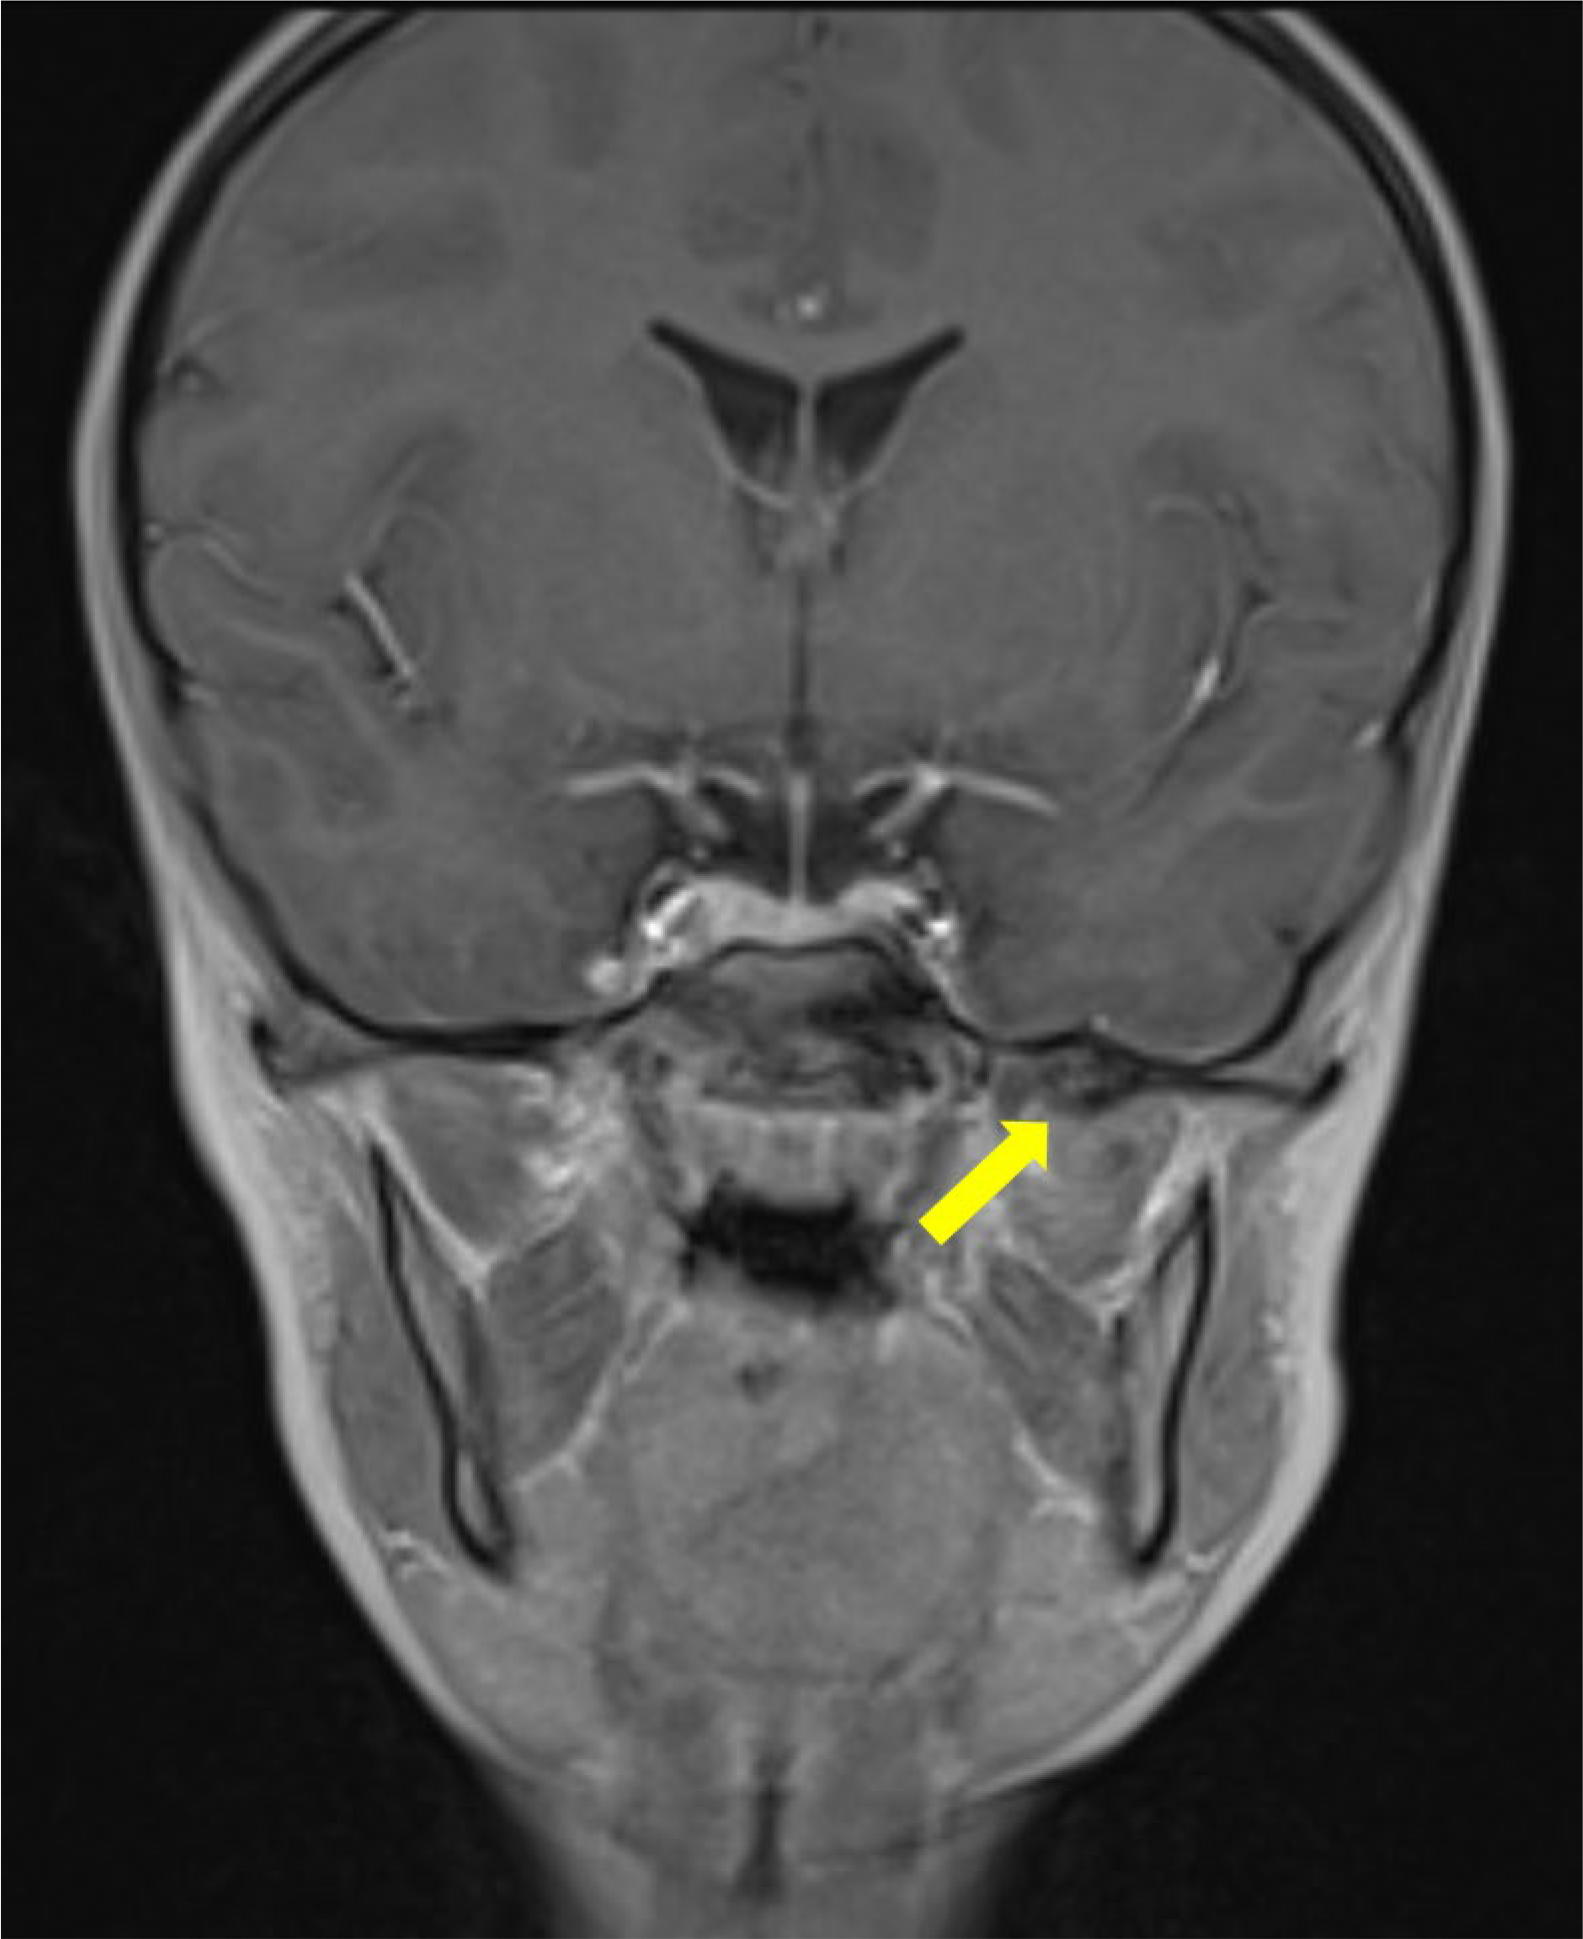

Magnetic resonance imaging (MRI) demonstrated a bony signal intensity of this ossified structure located between the left mandibular ramus and the spine of the left sphenoid (Figure 2). There was a reactive edema around the periphery of the structure, partially infiltrating the fibers of the lateral pterygoid muscle (Figure 3). There was an absence of a cartilaginous cap, suggesting an exostosis.

Figure 2

Contrast enhanced coronal T1 Dixon MRI scan showing the bony signal of the bony structure of the sphenoid spine (arrow) with no enhancement on the fat‑suppressed reconstructions (not shown).